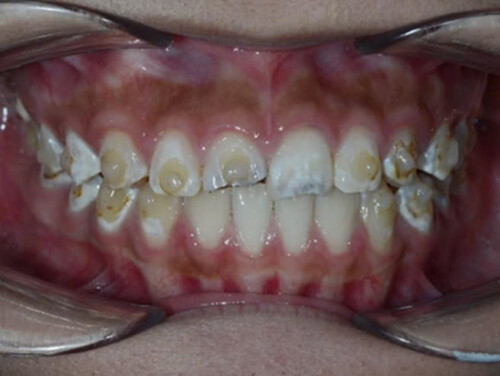

Hình 3: Tổn thương đốm trắng nặng hơn trên nhiều răng, xung quanh attachment